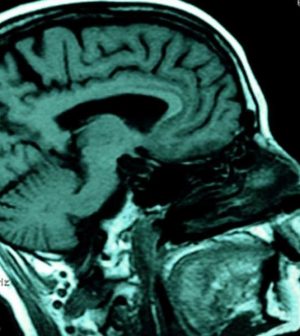

In the study, the researchers analyzed the brain tissue of 15 patients who had survived a year or more after a traumatic brain injury (TBI) and compared that tissue with brain tissue from 15 healthy controls. They found the TBI patients had higher levels of abnormal tau proteins.

An accumulation of abnormal tau proteins can cause brain cell damage and memory problems, the scientists explained.

The researchers also found that in mice, this type of abnormal tau spread from the site of the brain injury to other brain regions. This spread of tau was similar to the spread of prions, the infectious proteins associated with degenerative brain diseases such as Creutzfeldt-Jakob disease.

“This observation that a single brain trauma is associated with widespread tau deposition in humans and to the formation of a self-propagating form of tau in a relevant animal model provides the first evidence for how a mechanical brain injury might evolve into chronic degenerative brain disease, including CTE,” Zanier said in a University of Glasgow news release.